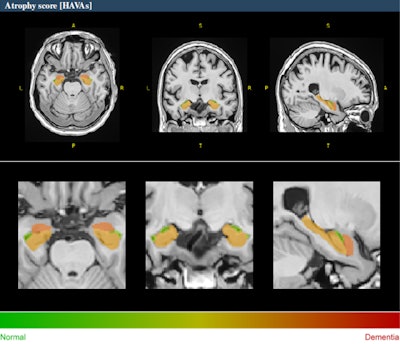

Example of HAVA score using the volBrain platform for a 70-year-old male with early mild cognitive impairment.

A novel deep-learning-based tool for Alzheimer's detection and mild cognitive impairment prognostic has been developed, relying on estimated lifespan trajectories of brain structures, the authors explained. Hippocampal-amygdalo-ventricular Alzheimer scores (HAVAs) are based on lifespan models of normal population and Alzheimer's patients, which after validation showed a great capability of detecting patients with Alzheimer's compared with control subjects and specific discrimination between progressive and stable mild cognitive impairment.

The pipeline is freely available and integrated into the volBrain online platform (see: volBrain: An Online MRI Brain Volumetry System, Front Neuroinform, 27 July 2016). It generates volumes of the hippocampus, amygdala, and inferior lateral ventricle, graphics showing where the patient's values stand between the estimated lifespan trajectories of healthy and Alzheimer's patients and it also calculates a probability score based on the three regions analyzed. The method has shown considerable accuracy both in the diagnostic task and the prognostic task.